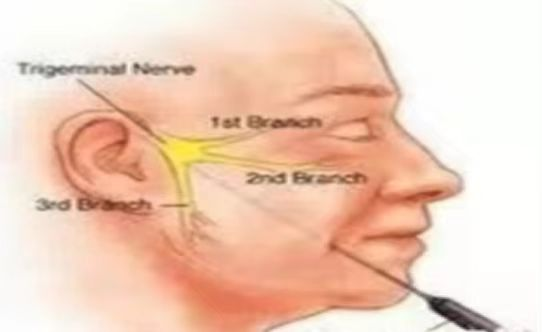

三叉神经痛又称“天下第一痛”,主要以单侧头面部反复发作、短暂性、电击样、烧灼样、刀割样等疼痛为特点,突发突止,一般历时几秒到数分钟,通常说话、咀嚼、洗脸、刷牙、吹风等时可诱发,常常累及三叉神经一个或多个分支。严重影响患者生活质量。具体病因目前不清楚,考虑:1.和神经伴行动脉血管关系太近,动脉搏动刺激神经,诱发疼痛。2.考虑神经自身病变引起。

射频热凝术

经过面部口角处将射频针穿刺到三叉神经半月节内,通过射频针发热,选择性毁损单支感觉神经,保留运动神经,达到止痛目的,术后面部稍麻木。

适合第II、III支单支发病患者。